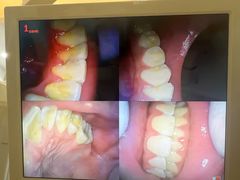

• 赫尔森口腔·牙齿种植修复

• -赫尔森口腔·牙齿种植修复

匿名用户 | 24-07-22